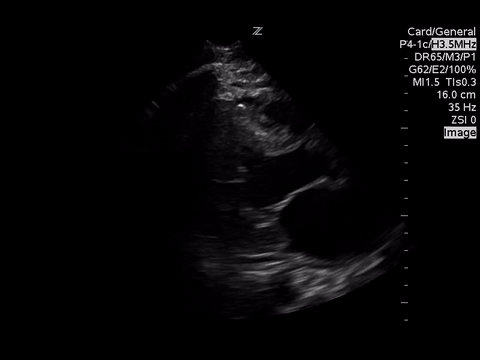

A focused echocardiogram was performed to try to differentiate between these causes. These are the images obtained:

| Parasternal Short Axis View at the level of the aortic valve |

Based on the parasternal long axis view, the LV walls are coming together at least 30% in systole, so the LV function appears normal. Also the mitral valve is almost making contact with the septum, which also confirms normal LV function.

A subxyphoid view is usually the most sensitive for looking for an effusion, but based on the views obtained there’s no effusion seen.